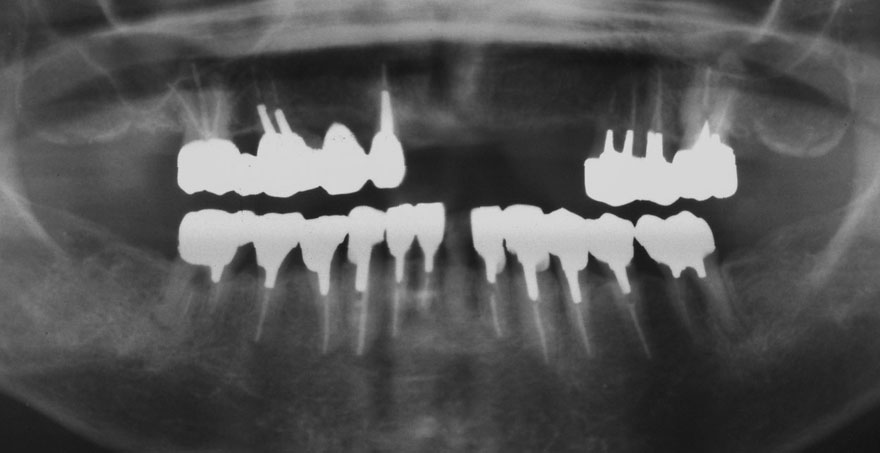

初診時 51歳 女性

31年後 82歳